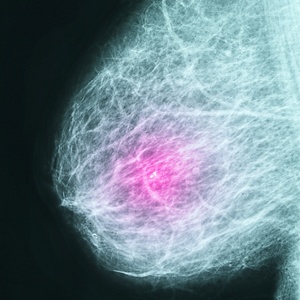

Notícias Post Title IA reduz diagnósticos tardios e detecta câncer de mama mais agressivo, diz estudo Deixe um comentário Deixe um comentário Cancelar respostaO seu endereço de e-mail não será publicado. Campos obrigatórios são marcados com *Comentário * Nome * E-mail * Site Salvar meus dados neste navegador para a próxima vez que eu comentar.